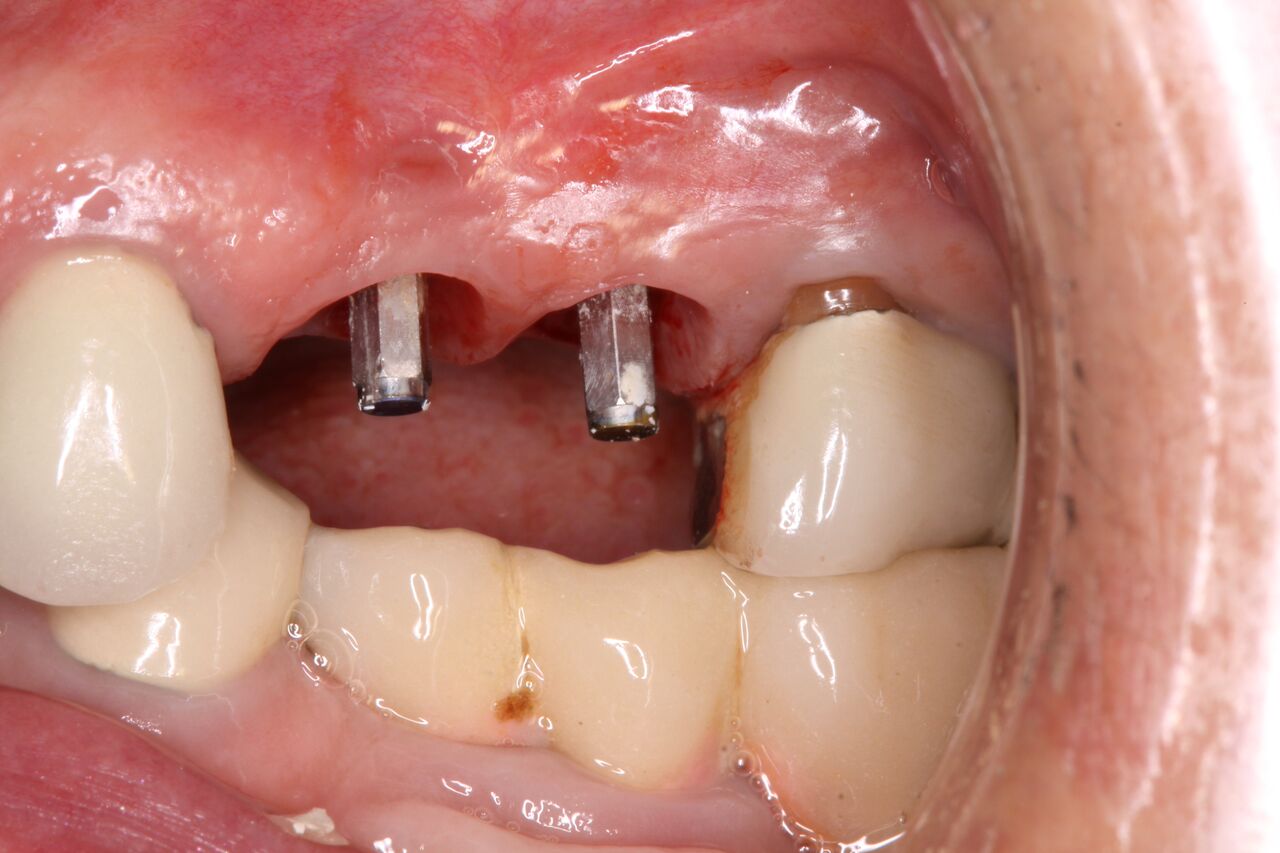

(14.) Integration confirmation on Nos. 12 and 13 at 6 months with temporary abutments and good soft tissue maturation.

Figure 14

A 67-year-old woman presented on an emergency basis with a bad odor and taste from crown No. 12, which had been diagnosed that day at hygiene recall as decayed and no longer attached to the underlying root (Figure 8 and Figure 9). The patient was anesthetized and the existing bridge was sectioned (Figure 10), leaving crown No. 14 intact. The No. 12 root was extracted and the site was fully debrided of granuloma. A platform shift implant was stabilized in excess of 45 Ncm in position No. 12, which was prosthetically correct. The soft tissue of pontic site No. 13 was contoured to mimic soft tissue contours of a bicuspid and an implant was secured in excess of 45 Ncm. Implant No. 13 was milled to allow for unimpeded seating of the temporization abutment, whereas implant No. 12 did not need milling as it was a platform-shift implant. The existing crown No. 12 and cantilever No. 13 were revised to be a temporary bridge on Nos. 12 and 13 (Figure 11 and Figure 12). The revised temporary bridge was positioned in infraocclusion and cemented after the extrusion of excess cement extraorally (Figure 13). No bone graft or sutures were placed as the temporary crowns sealed the sockets.

The patient was prescribed antibiotics and analgesics and instructed in postoperative care particular to immediately provisionally restored implants. At 6 months, integration was confirmed (Figure 14) and the patient returned to her dentist for restoration. The implants were restored with individual cement-retained crowns with a platform shift for No. 12 restoration from the 6-mm diameter of the implant to a 5-mm diameter of the final restoration (Figure 15 and Figure 16).